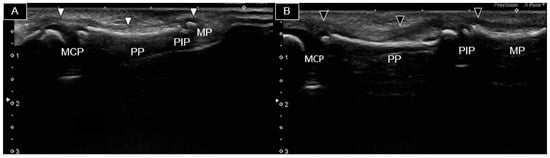

Transverse views of distinct segments of the right second finger, from proximal to distal, are shown in Figure 3.

Figure 3. Ultrasound images depicting the palmar aspect of the right 2nd finger in the long axis (A) and at distinct segments (arrowheads) progressing from proximal to distal in the short axis (BD). MCP, metacarpophalangeal joint; PP, proximal phalanx; PIP, proximal phalangeal joint; MP, middle phalanx; MH, metacarpal head.